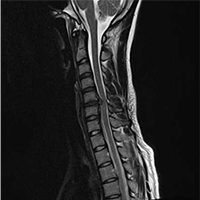

• Normal Cervical

MRI

• Cervical Disc

Herniation at C5/C6